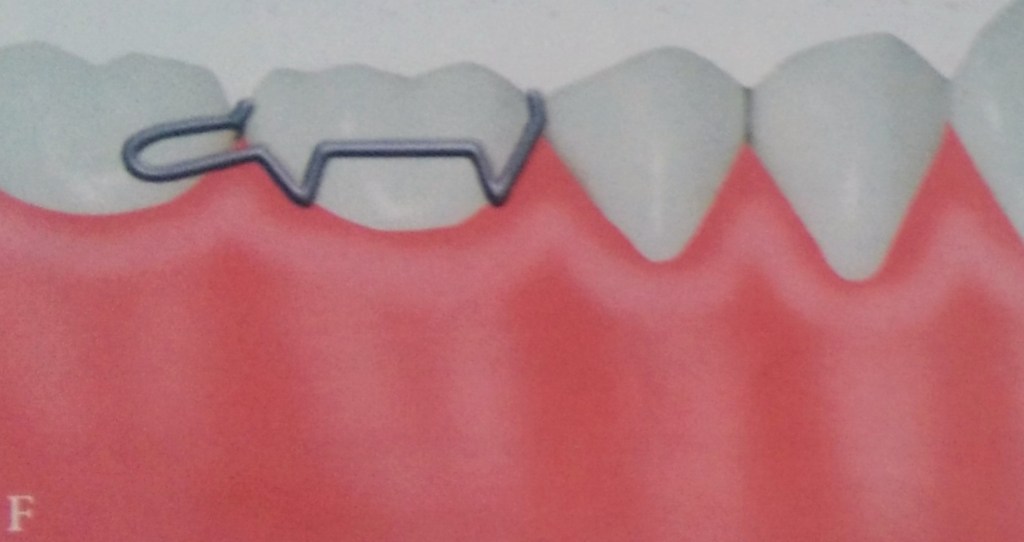

ADAMS CLASP

• The Adams clasp was first described by Professor Phillip Adams.

• It is also known as Liverpool clasp, universal clasp and modified arrowhead clasp.

• When properly constructed this clasp offers maximum retention.

• The clasp is constructed using 0.7mm hard round stainless steel wire.

The Adams clasp is made of the following parts:

a) Two arrowheads

b) Bridge

c) Two retentive arms.

The two arrowheads engage the mesial and the distal proximal undercuts.

The arrow head are connected to each other by a bridge that is at 45° to the long axis of the tooth.